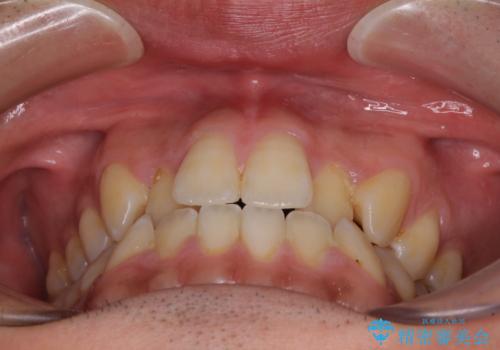

ワイヤー矯正を併用したインビザライン矯正治療

- 前歯のデコボコを気にして来院された患者様です。

歯列としてはワイヤー装置でもインビザラインでも対応可能でしたが、インビザラインが苦手とする上顎側切歯(真ん中から2番目の歯)の舌側転位が顕著でした。

治療の確実性を上げるために、インビザライン開始前に上顎のワイヤー装置にて舌側転位を解消し、その後インビザラインにて矯正治療を行うこととしました。

前歯のデコボコが早めに改善され、スムーズに治療を終えることができました。